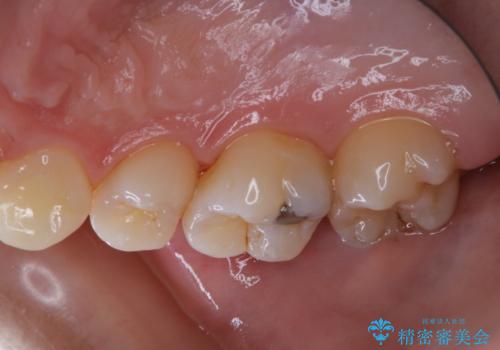

治療の前にPMTCできれいでツルツルな歯に

- 今後治療を進めていく予定で、まずはきれいにクリーニンングから行いたいとのことでした。PMTC60分コースを行いました。

PMTCを行う際には担当の歯科衛生士が、患者様1人1人の虫歯・歯周病などのリスク・ブラッシングスキルなどを確認します。

単なる磨き方の指導だけではなく、歯並びや歯肉の状態、ライフスタイルなどにより、患者様に適した歯ブラシや歯磨剤の選択をしたり、お口のお悩みについてのご相談も承っております。

定期的にPMTCでメンテナンスを行うことで、なにかあった時の早期発見につながります。

日々の磨き残しや唾液の成分などによりバイオフィルムや歯石はどうしても付着してしまいます。歯石や汚れを放置していると、そこで病原菌が繁殖す始めます。歯肉に炎症が生じると歯周病などの引き金となります。

そのため、2~3か月に1回は、歯科医院での専門的クリーニングをすることが大切です。